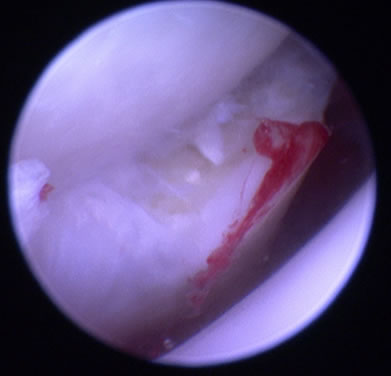

関節鏡検査

関節鏡視下で軟骨フラップを切除します。大型犬の成長期の跛行は消炎鎮痛剤等による対症療法ですませず、跛行原因の早期診断、早期治療が重要です。